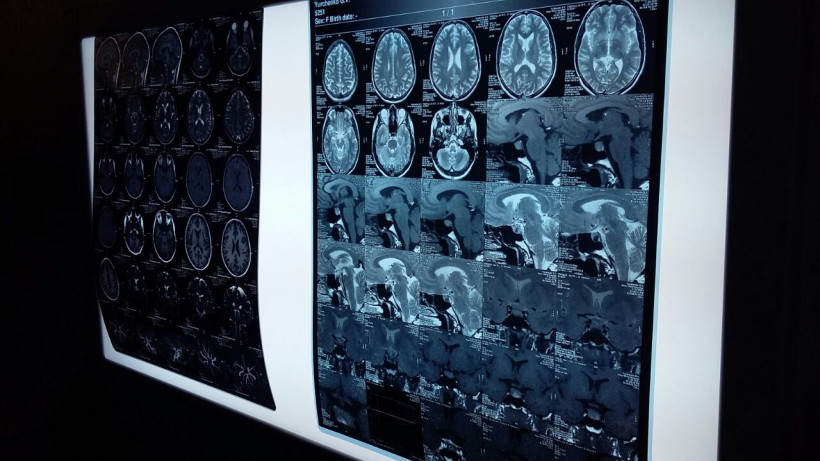

Магнитно-резонансная томография позволяет обследовать все органы в человеческом теле и выявлять патологии на самых ранних стадиях, следовательно, более быстро и правильно ставить диагноз пациентам. Как отмечают специалисты, оборудование, которое установили в столице Приамурья, не уступает лучшим мировым стандартам.

— К счастью, у нас все получилось, — рассказала генеральный директор МРТ-центра Мария Трунова. — Я сама врач-рентгенолог, мне всегда хотелось, чтобы в этой области амурская медицина развивалась. С мая начали строить МРТ-центр в Благовещенске. Закупили современное оборудование, одно из лучших в мире на сегодняшний день. Теперь мы можем досконально исследовать сердце, мозг, позвоночник на самом современном уровне.

— У амурчан есть большая потребность в МРТ исследованиях, — отметил главный внештатный специалист по лучевой и инструментальной диагностике министерства Алексей Побережский. — Мы надеемся, что данный вид диагностики станет более доступным для амурчан. Важно, что данный аппарат позволит обследовать пациентов с эпилепсией и другими серьезными заболеваниями центральной и периферической нервной системы. Это не первый аппарат МРТ в Благовещенске, но то, что он самый современный на Дальнем Востоке и один из лучших в России — точно.